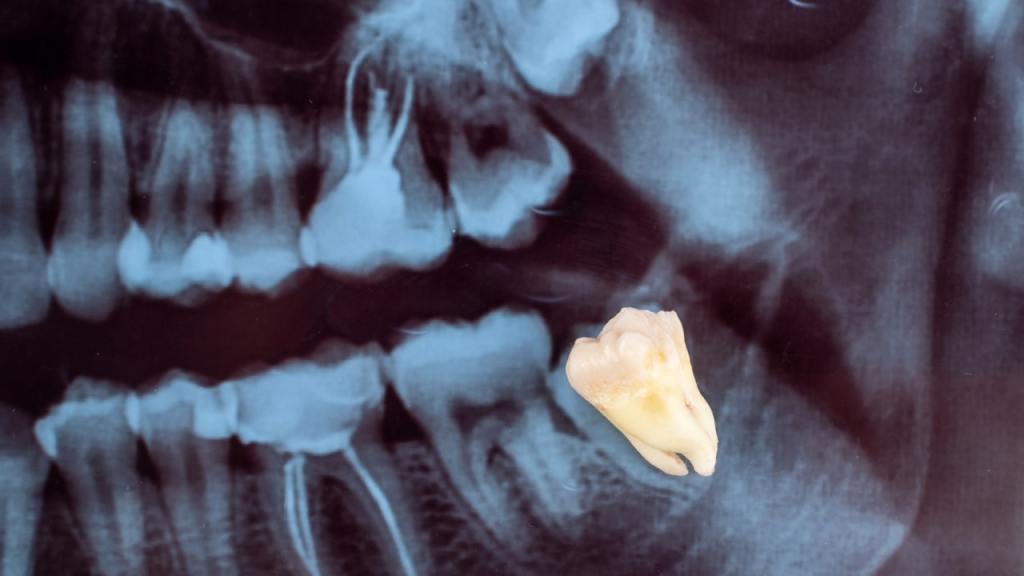

Wisdom Tooth Extractions

Wisdom teeth often cause complications such as impaction, crowding, or infections.

We offer surgical removal of wisdom teeth using advanced techniques that minimize healing time and reduce post-operative discomfort.